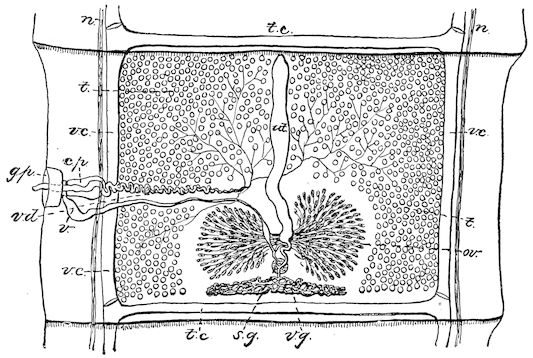

Fig. 8.—Transverse section through the middle region of the face in a pig suffering from osseous cachexia.

18In the final stages, the bones may be cut with a knife, and a time arrives when bony tissue seems completely to have disappeared; thus, as shown in Fig. 8 herewith, it was possible to cut the entire head of a pig into thin slices without the slightest difficulty. All parts of the head had been affected by the softening change.

From the chemical point of view, the diminution in mineral salts and in phosphate of calcium has long been recognised, but the degree of this change varies according to the phase. In human beings the proportions have been estimated as follows: Normal bone, 50 to 80 per cent. of phosphate of calcium; bone in persons suffering from osteomalacia, 5 to 20 per cent. of phosphate of calcium. The changes in the ossein have not been carefully studied. We only know that histologically the ossein becomes fibrillar, and that chemically it no longer retains its normal composition.